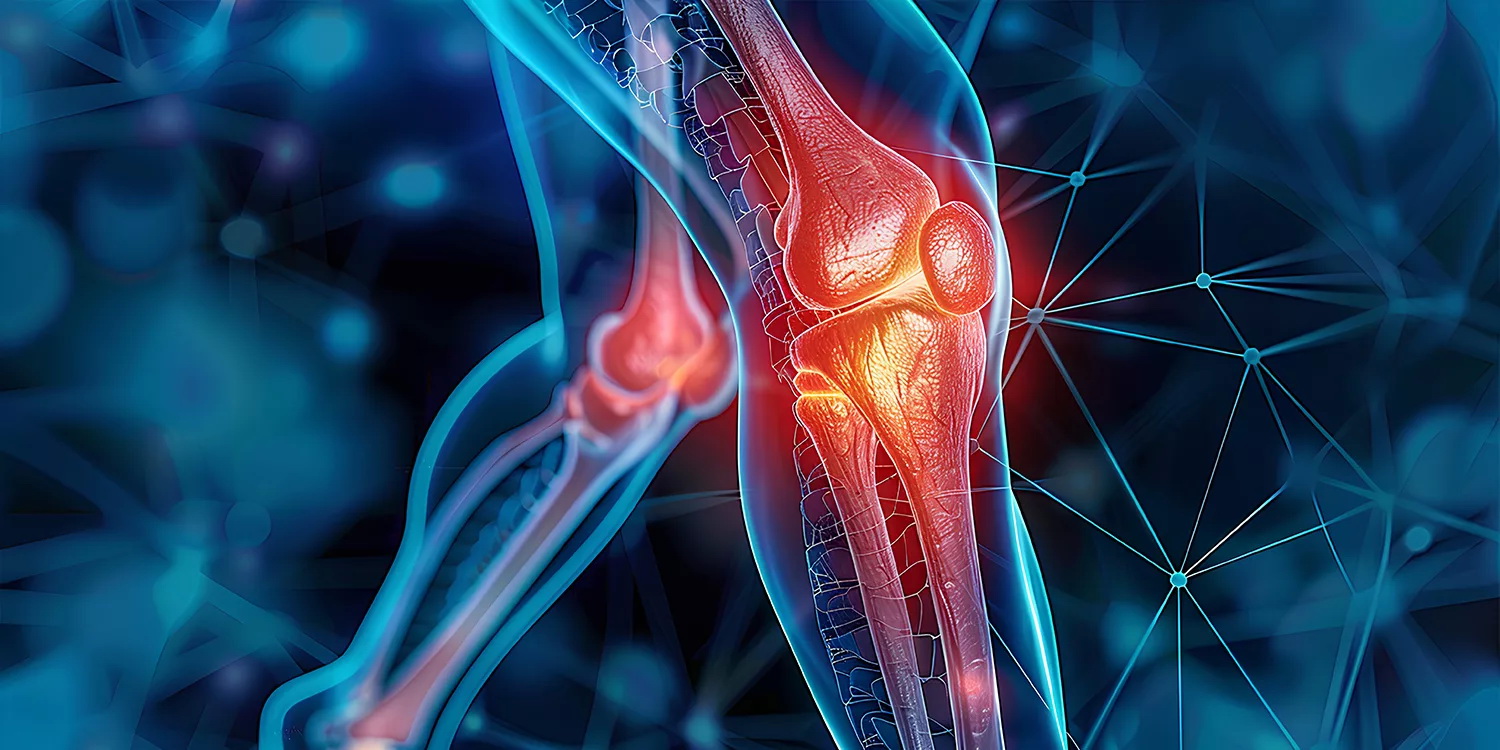

Dar vadinamas piogeniniu arba bakteriniu, toks artritas paprastai smogia didiesiems sąnariams – klubų, kelių. Bet gali nusitaikyti į kitus, pavyzdžiui, pečių sąnarius ar kulkšnis.

Kol sąnariai dar savi – tai yra ne protezai, – septinis artritas, kaip minėta, dažniausiai taikosi į kelius, klubus, pečius, kulkšnis, alkūnes, riešus.

Išsivysčius septiniam artritui, audiniuose aplink kelio sąnarį ima kauptis skysčiai ir jis ištinsta – tai vadinama sąnario efuzija. 91 proc. asmenų, kuriems septinis artritas, ji nustatoma paprastu ultragarso tyrimu.